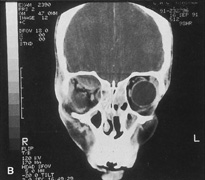

surface of the lateral rim.  Fig. 7. Coronal schematic view demonstrating major vessels penetrating periorbita

and traversing the extraperiosteal space that may be encountered during

periorbital elevation. (A, zygomaticotemporal artery; B, zygomaticofacial artery; C, communicating branch of infraorbital artery: D, supraorbital artery: E, posterior ethmoidal artery: F, anterior ethmoidal artery.) Fig. 7. Coronal schematic view demonstrating major vessels penetrating periorbita

and traversing the extraperiosteal space that may be encountered during

periorbital elevation. (A, zygomaticotemporal artery; B, zygomaticofacial artery; C, communicating branch of infraorbital artery: D, supraorbital artery: E, posterior ethmoidal artery: F, anterior ethmoidal artery.)